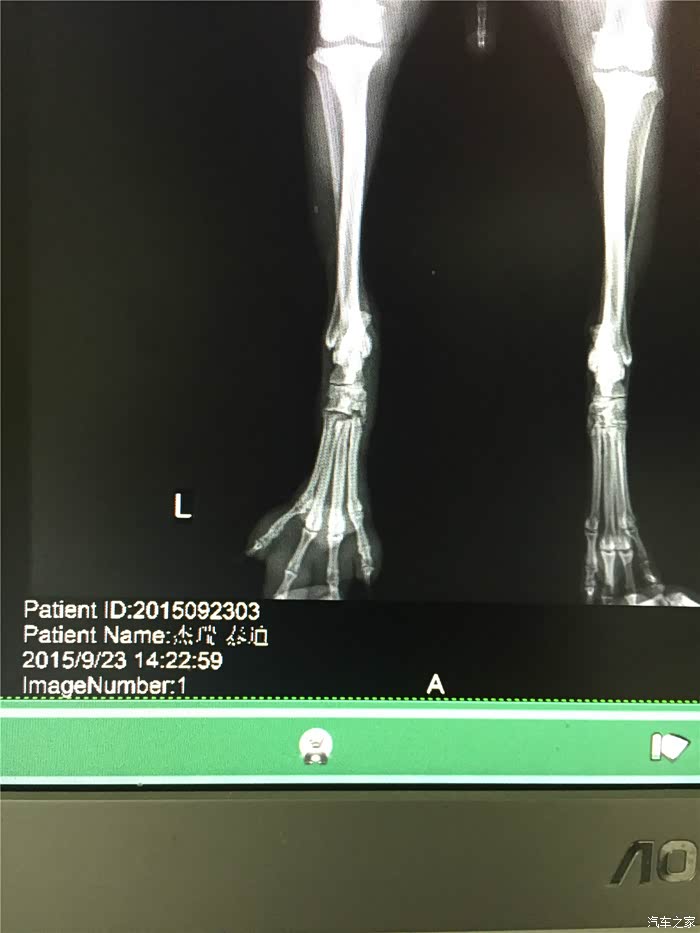

回拉萨途中,dido妈已经告诉我,他们找到了一家宠物医院,是拉萨警犬指定医院,有dr设备,据说比X光更好

上海的医生朋友也说,dr设备还是比较先进的,看的比较清楚

拍片。果然是骨折了,但是并不算严重,骨头甚至没有完全断开。

医生建议外部固定,静养恢复。

询问了上海的宠物医生,把dr图拍下给他看过,也说可以外部固定。